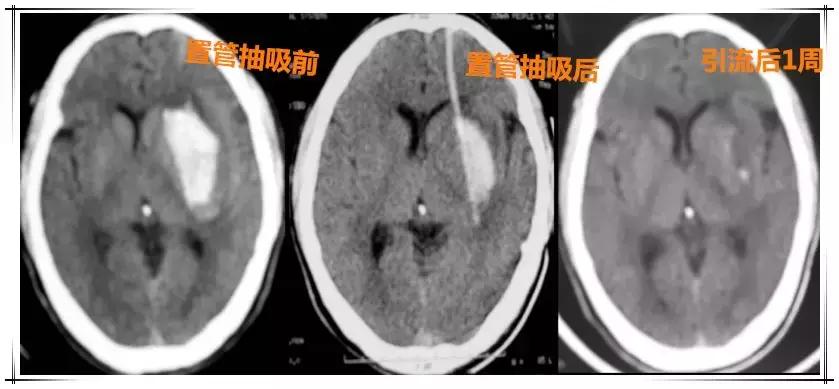

78岁的张婆婆,患有高血压、糖尿病、肺心病。突发脑出血,左侧基底节区血肿,危及生命,需要急诊手术治疗。但张婆婆年老体弱,长期患多种慢性病,不能接受全身麻醉及传统开颅手术。科室在局部麻醉下给张婆婆做了微创锥颅置管软通道颅内血肿抽吸引流术。张婆婆很快脱离了生命危险,恢复了健康。

又来看哈这个微创手术是咋个把脑壳儿里面的血吸出去滴!

ps:看到片子里那个白色一坨坨的东西了吗?那个就是出血区域哦,引流后1周就没有了~~